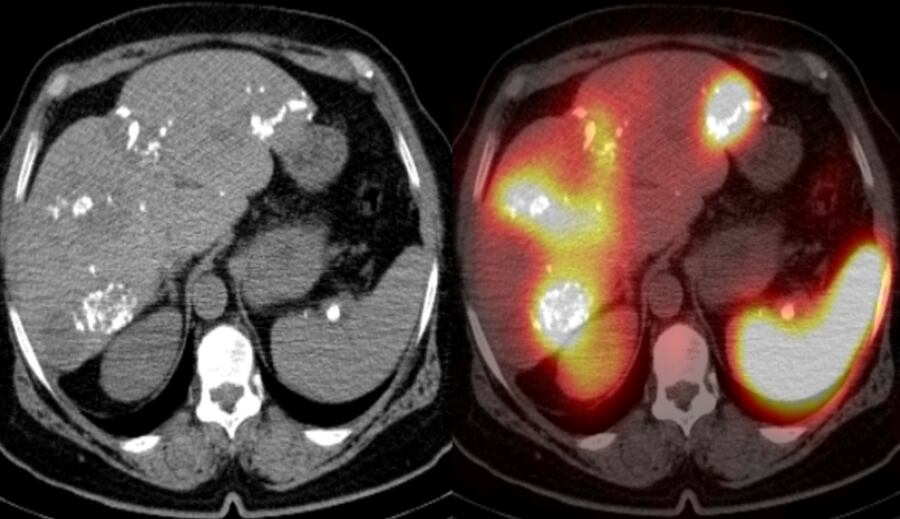

El médico nuclear realiza tomografías especiales, como una foto en 3D, que utiliza radiofármacos.

Entonces, la tarea de un médico nuclear es tomar al paciente e inyectarle el radiofármaco. Esa sustancia va por su sangre, irá a juntarse a algún tejido de interés y lo va a poner a “brillar”. Dependiendo del tipo de radiofármaco que yo utilice, puedo diferenciar varias cosas en el cuerpo.

Posteriormente, esa radiación que emite la sustancia es leída por el equipo y transformada en imágenes. Entonces, esto es muy útil en cáncer. Cada vez se siguen creando más y más tipos de radiofármacos para diferentes estudios. Casi que todos los días se crea algo nuevo.

El más clásico, y lo que más representa el grueso de los estudios, es el cáncer. Su relevancia está en ofrecer un mejor diagnóstico, estadio y tratamiento.